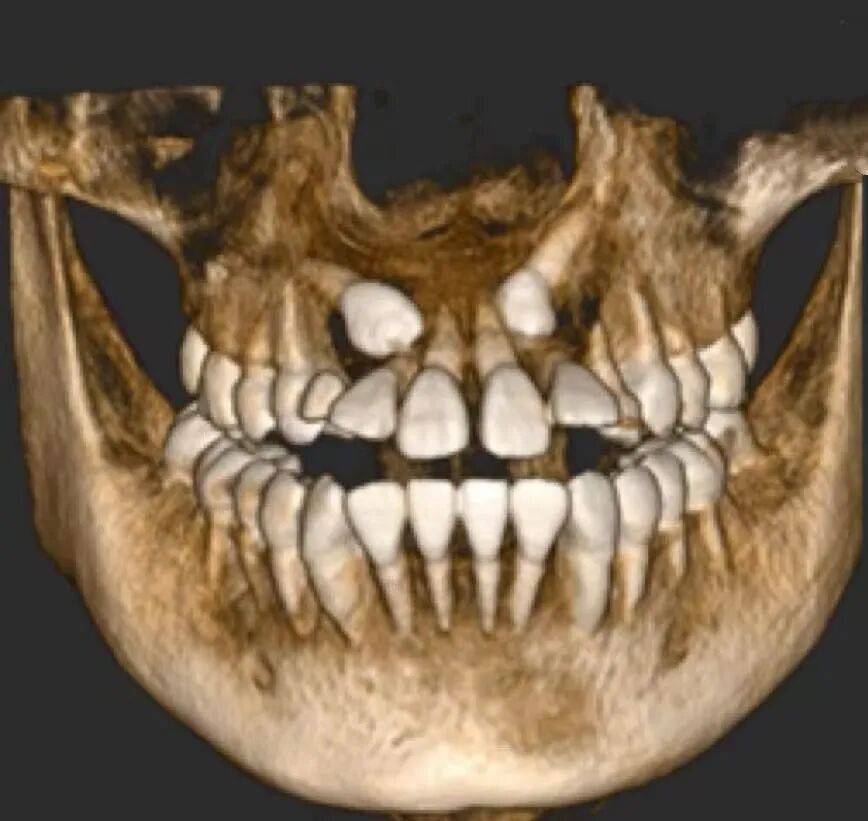

简单来说,埋伏牙就是牙齿在萌出的过程中,因为各种原因没能顺利长到口腔里,而是 “藏” 在了颌骨里面。这就好比一颗种子被种下去后,却始终没有破土而出,默默待在土壤里一样。

值得庆幸的是,随着多学科联合治疗的开展以及正畸技术的不断发展与完善,更多的上颌前牙埋伏阻生齿得以矫治和保留。通过正畸 - 外科联合牵引助萌复杂埋伏阻生牙的方法,往往能获得良好的效果,帮助患儿健康自信地成长。

如果大家怀疑自己有埋伏牙,一定要及时去正规的口腔医院进行检查。通常情况下,拍个 X 光片就能清楚地看到牙齿的情况了。